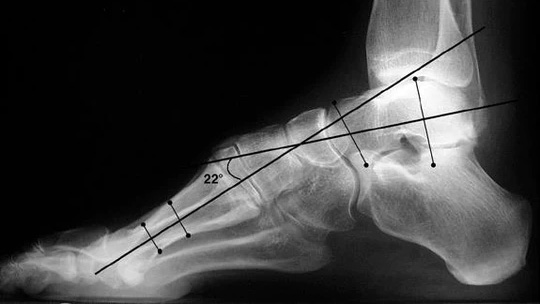

In the meantime, there is a notable lack in both the understanding and pre-surgical treatment of the high arch or cavovarus foot alignment and especially the subtle cavovarus foot and its symptoms.’ Like flatfoot, high arches are a common deformity leading to significant, under-treated symptoms.

The cavovarus foot typically overloads or puts too much pressure on the first metatarsal head or the ball of the foot behind the big toe. It also tends to tilt the heel so that the pressure is on the outside of the heel and can cause pressure along the outside of the middle foot. This tends to lead to tendon problems, stress fractures, and ankle sprains, as well as potential structural problems to include the knees, hip, and lower back.

If a patient has a high arch, walks on the outside of their foot, or feels undue pressure on the ball of their foot, then using a typical orthotic will accentuate or worsen the deformity and can lead to several problems from overcorrection. The high arch, cavovarus foot needs to be adjusted in directions opposite to the typical orthotic, while having specific features to best address symptoms.